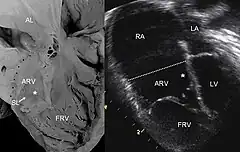

![]() Ecocardiografia de una anomalía de Ebstein: Abreviaturas: RA: aurícula derecha; LA: aurícula izquierda; ARV: ventrículo derecho atrializado; LV: ventrículo izquierdo. | ||

El diagnóstico se sospecha por los síntomas y la exploración del paciente. Se confirma mediante la realización de una ecocardiografía del corazón.